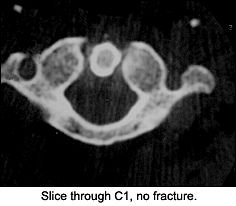

On the CT scan through the C1-2 vertebrae, note the fracture through the dens and the lateral mass of C2. (That was the depression we saw on the APOM of the lateral mass.) Should we look at the APOM view again?

This view above evaluates C1-C2, which cannot be visualized clearly on the lateral. The most important element to check is the alignment of the lateral masses of C1. The intervertebral space should be symmetric. The dens can also be evaluated for fracture in this view, but occasionally overlying shadows may give the false impression of a dens fracture (Mach effect). Correlate the findings with the lateral view of the cervical spine. The incidence of fractures to the axis is about 6 percent, and over 50 percent of those fractures involve some part of the dens.